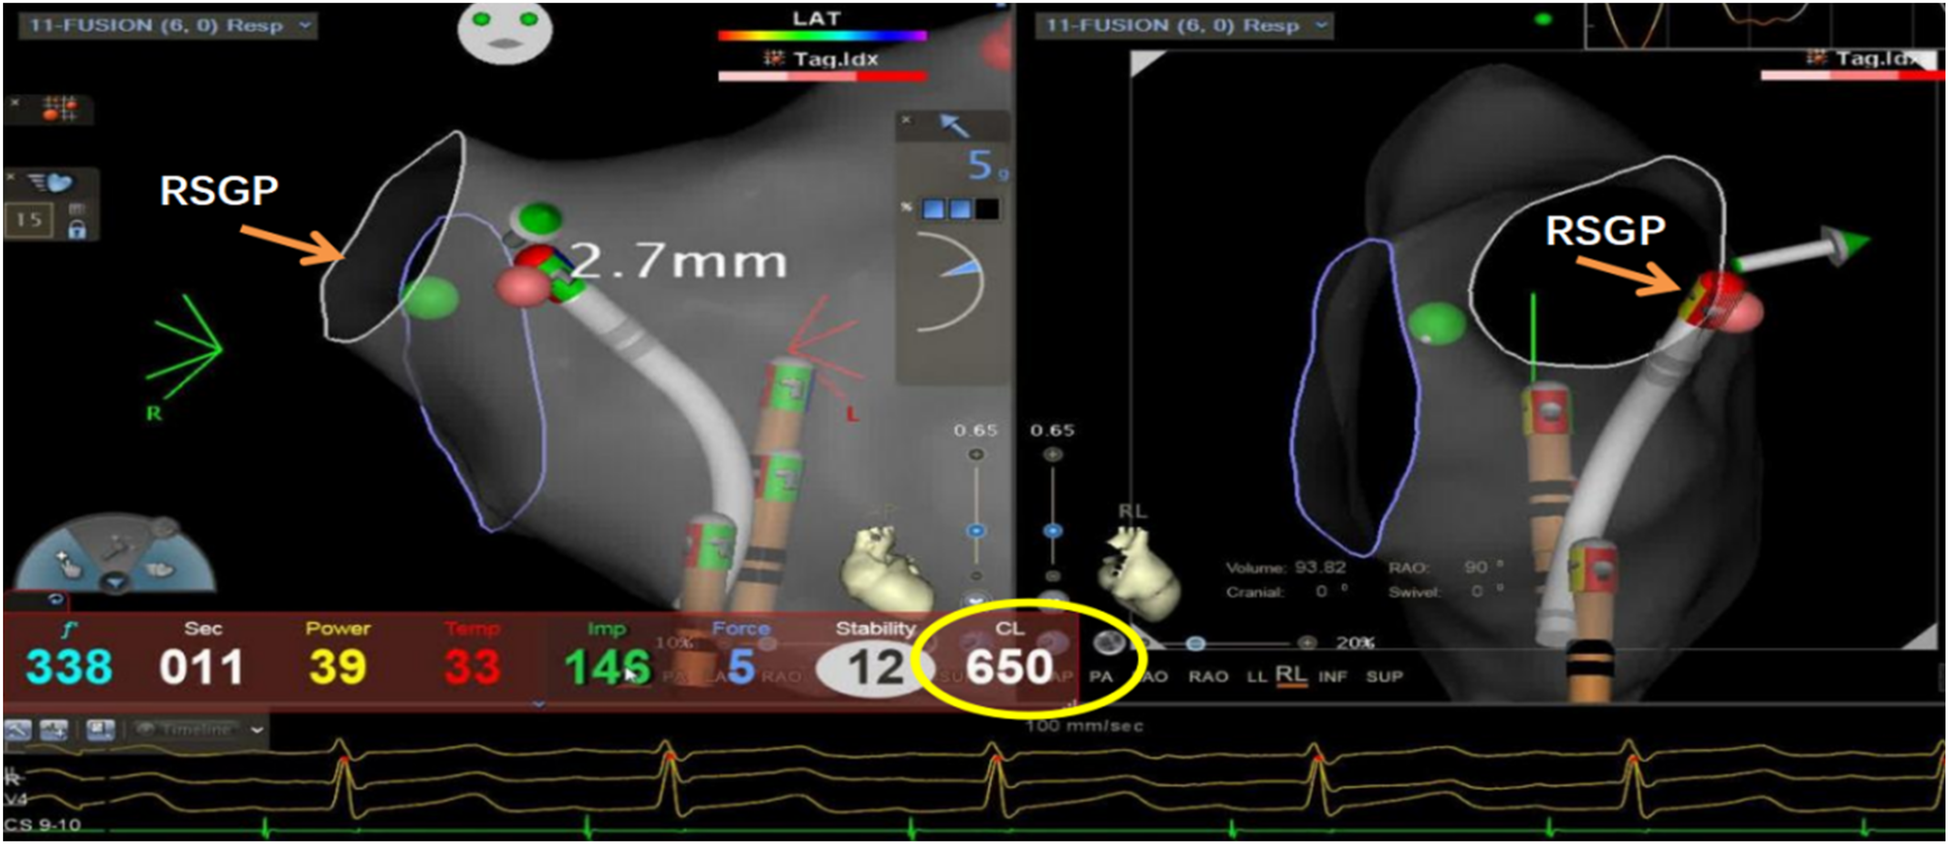

This study utilized the Carto electrophysiological navigation system (CARTO3, FG-5400-00C, USA) for cardiac modeling and ablation. Under intracardiac ultrasound guidance, a right atrial model was established, and three-dimensional fossa ovalis positioning was performed. Zero-ray transseptal puncture was carried out, and the SL1 sheath was advanced into the left atrium, as shown in Figure 2. Using the left atrial model for guidance, GP ablation was performed based on anatomical localization (temperature-controlled at 43°C, 40-watt discharge, with cold saline irrigation). During GP ablation, vagal responses including significant sinus bradycardia, sinus arrest, and atrioventricular block were observed, as shown in Figure 3. Ablation sites were marked, and ablated around these points reinforcely until vagal responses were no longer elicited. GP ablation was sequentially performed in the left superior GP (LSGP), left inferior GP (LIGP), right superior GP (RSGP), and right inferior GP (RIGP), as illustrated in Figure 2B. If five consecutive ablations within a GP region failed to induce any vagal response, the procedure proceeded to the next GP region. In most cases (80%), if the sinus rhythm gradually increased to approximately 90 beats per minute during ablation of the right superior pulmonary vein GP, ablation in that area was terminated at that point, as shown in Figure 4. The increase in sinus rhythm, disappearance of vagal reflexes, and completion of anatomical ablation signified the end of the procedure. Electrophysiological studies (EPS) demonstrated that the sinoatrial node recovery time and AV Wenckebach point were significantly shortened postoperatively compared to preoperative values, as shown in Figure 5.

Figure 4. Ablation of the left atrial right-superior ganglionated plexus (RSGP) resulted in a gradual increase in sinus heart rate to approximately 92 beats per minute (RR interval 650 ms), after which the procedure was terminated.